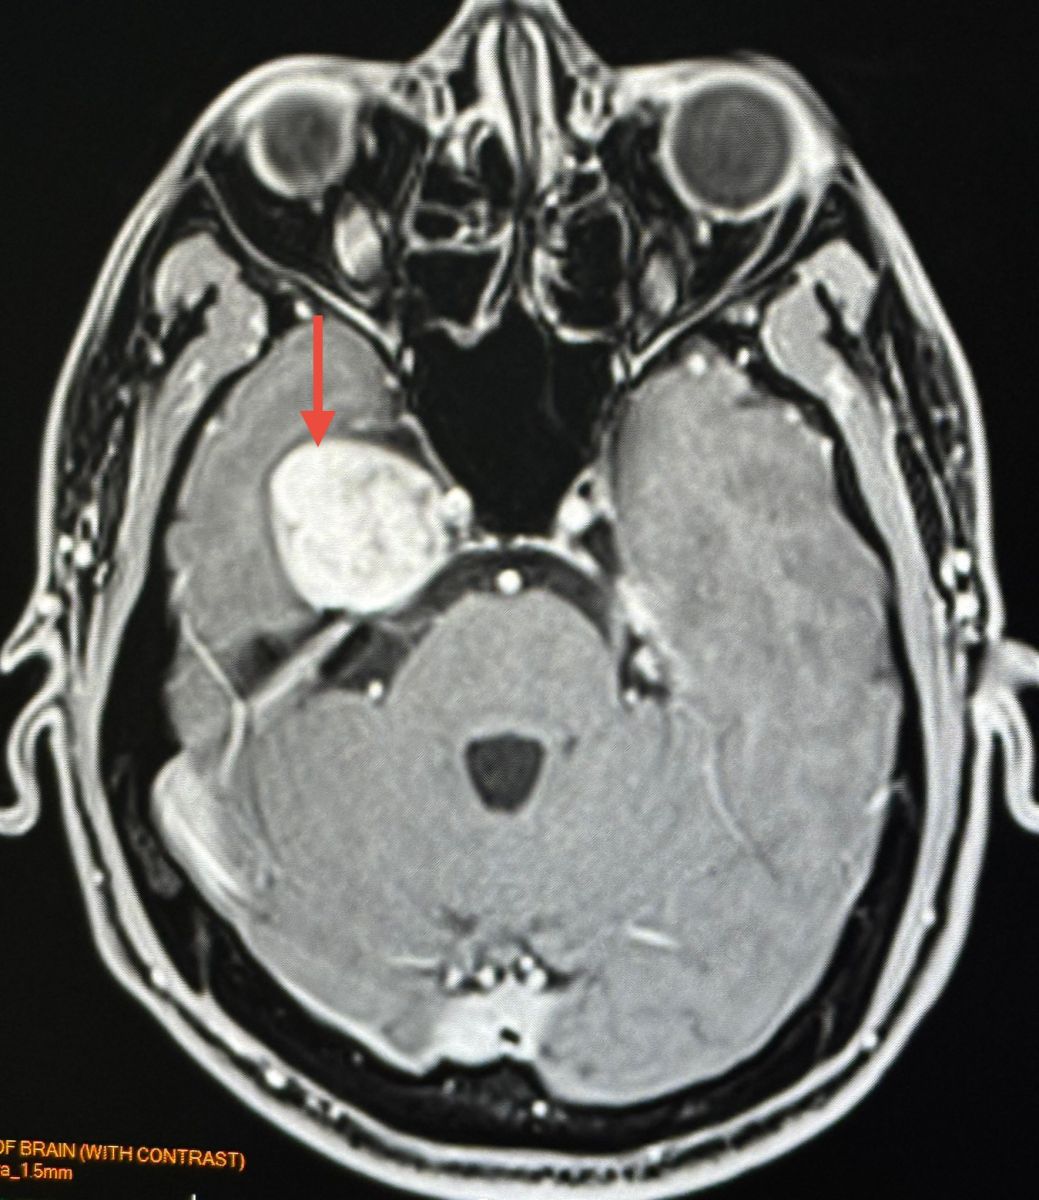

ทำคอมพิวเตอร์ CT สมองพบก้อนขนาด 2.7 × 3.0 × 2.9 เซนติเมตร ที่กลีบขมับของสมองด้านขวา right temporal lobe ทำ MRI (Magnetic Resonance Imaging) โดยใช้คลื่นแม่เหล็กไฟฟ้าและคลื่นวิทยุความถี่สูงและฉีดสี พบก้อนขนาด 3.1 × 2.9 × 2.9 เซนติเมตร สงสัย Trigeminal Schwannoma เนื้องอกของปลอกประสาทเส้นประสาทสมองเส้นที่ 5 ข้างขวา

Trigeminal Schwannoma คือเนื้องอกชวานโนมาที่เกิดจากเซลล์ชวานน์ (Schwann cells) ซึ่งเป็นเซลล์ที่ทำหน้าที่สร้างเยื่อไมอีลินที่ห่อหุ้มเส้นประสาท โดยเนื้องอกชนิดนี้เกิดขึ้นบริเวณเส้นประสาทไทรเจมินอล ซึ่งเป็นเส้นประสาทสมองเส้นที่ 5 เนื้องอกชนิดนี้พบน้อยมากๆ ส่วนใหญ่เป็นเนื้องอกไม่ร้ายแรง (benign) โตช้า รักษาด้วยการผ่าตัด หรือฉายแสง